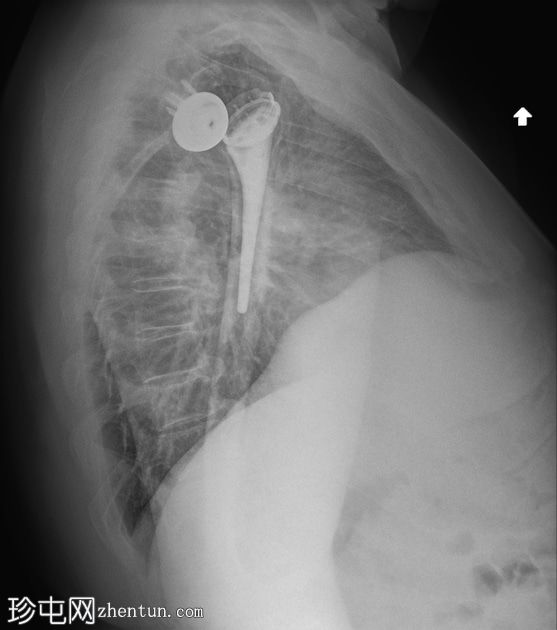

左肩

X光片

3.jpg

正面 - 内旋

全肩关节置换术后肱骨假体前脱位,伴假体分离。